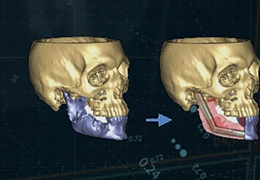

The surface reconstruction procedure starts with a sphere (recursively tesselated icosahedron) or a rectangle, which slowly wraps around a (segmented) volume data set. In order to avoid topological defects and to let the surface smoothly grow into deep sulci, a dynamic mesh algorithm was developed which automatically invents new polygons on the fly at places where they are needed. A reconstructed cortical surface may be inflated, cut interactively and slowly unfolded minimizing areal distortions. Statistical 3D maps may be superimposed on reconstructed, inflated or flattened cortex. Signal time courses may be invoked by simply pointing to any region of a visualized surface.

Mesh Manipulation

Fast and interactive surface slicing, cortex inflation and unfolding in real-time.